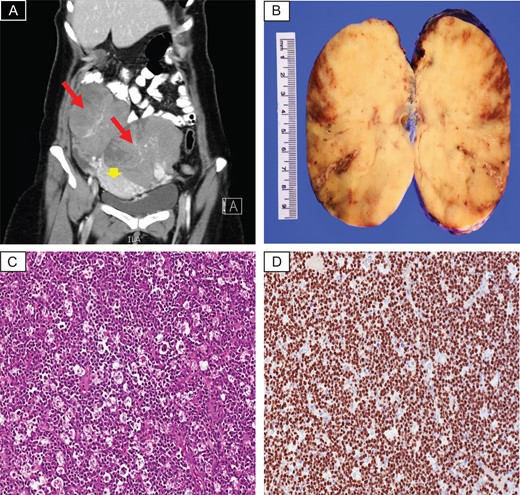

(A) CT scan with contrast revealed large bilateral lobulated heterogeneous adnexal masses (red arrows), displacing the uterus down (arrow head). (B) Gross photo showing homogenous white tan cut surface, focal areas of hemorrhage and necrosis are seen. (C) Histopathology examination demonstrates sheets of diffuse lymphoid infiltrate with prominent starry-sky appearance (H&E; ×20). (D) Ki67 proliferative index is almost 100% (×20).

The patient underwent total abdominal hysterectomy with bilateral salpingo-oophorectomy. The specimen sent for pathologic evaluation. We received two separate adnexal masses, the right adnexal tissue composed of a single solid capsulated mass with smooth tan lobulated cut surface weighing 564 g and measuring 12 × 10 × 6 cm3. The left adnexal tissue composed of a single solid mass weighing 1040 g and measuring 15 × 10 × 7 cm3, with homogenous white tan lobulated cut surface, focal areas of hemorrhage and necrosis were seen (Fig. 1B). Microscopic examination of the sections taken from both masses revealed sheets of diffuse lymphoid infiltrate composed of medium sized lymphoid cells with minimal amphophilic cytoplasm, prominent basophilic nucleoli, coarse chromatin and thick nuclear membrane. Prominent starry sky pattern with numerous mitosis and apoptosis seen (Fig. 1C). By immunohistochemistry, the tumor cells revealed positive immunoreactivity against CD79a, CD20, PAX-5, CD10, BCL6 while negative for BCL2, CD3, CD5, CD21, CD23, CD1a, TdT and Cyclin D1. Ki67 proliferative index of 100% expressed in the tumor cells (Fig. 1D). Flow study result showed small lymphoid population expressing CD19, CD20, CD22 and CD10. In the meantime, FISH interpretation revealed positive BCL6 rearrangement and c-MYC (8q24) rearrangement. IGH/BCL2 [t (14; 18)] rearrangement was not detected. All of the above ancillary studies were consistent with the diagnosis BL. The patient planned to be treated with multi-agent chemotherapy R-CODOX and R-IVAC chemotherapy. Our patient currently is on her third cycle, doing well and alive.